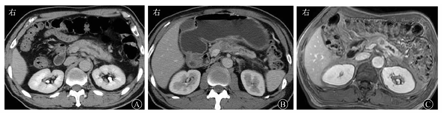

文献报道MSCT检测胰腺癌的敏感度可达90%以上[5,6]。胰腺癌通常在CT图像上表现为边界不清的实性肿块,相对正常胰腺实质略微低密度。胰腺癌合并急性胰腺炎的直接征象是胰腺轮廓扭曲,异常增多的软组织肿块突出于胰腺轮廓外,侵入相邻器官和(或)血管结构,增强呈轻度强化(图1A、图1B);如果同时发现淋巴结肿大或肝转移,则可以确立诊断。

在慢性胰腺炎中可见到胰管穿过肿块,在胰腺癌中胰管表现为不规则狭窄或完全阻塞。DWI和动态增强MRI能够区分肿瘤组织和水肿性纤维化[10,11,12,13,14]。多b值体素内非相干运动(intravoxel incoherent motion,IVIM)方法已经应用于胰腺成像,并且已有鉴别胰腺癌和正常胰腺的有价值的研究结果[15]。动态增强MRI提高了胰腺和肿瘤的信号强度差异,有利于小胰腺癌的检出(图1C),也可以用于区分胰腺癌与由慢性胰腺炎引起的局部肿块,有利于检出长期慢性胰腺炎癌变或合并的胰腺癌[13,14,16]。